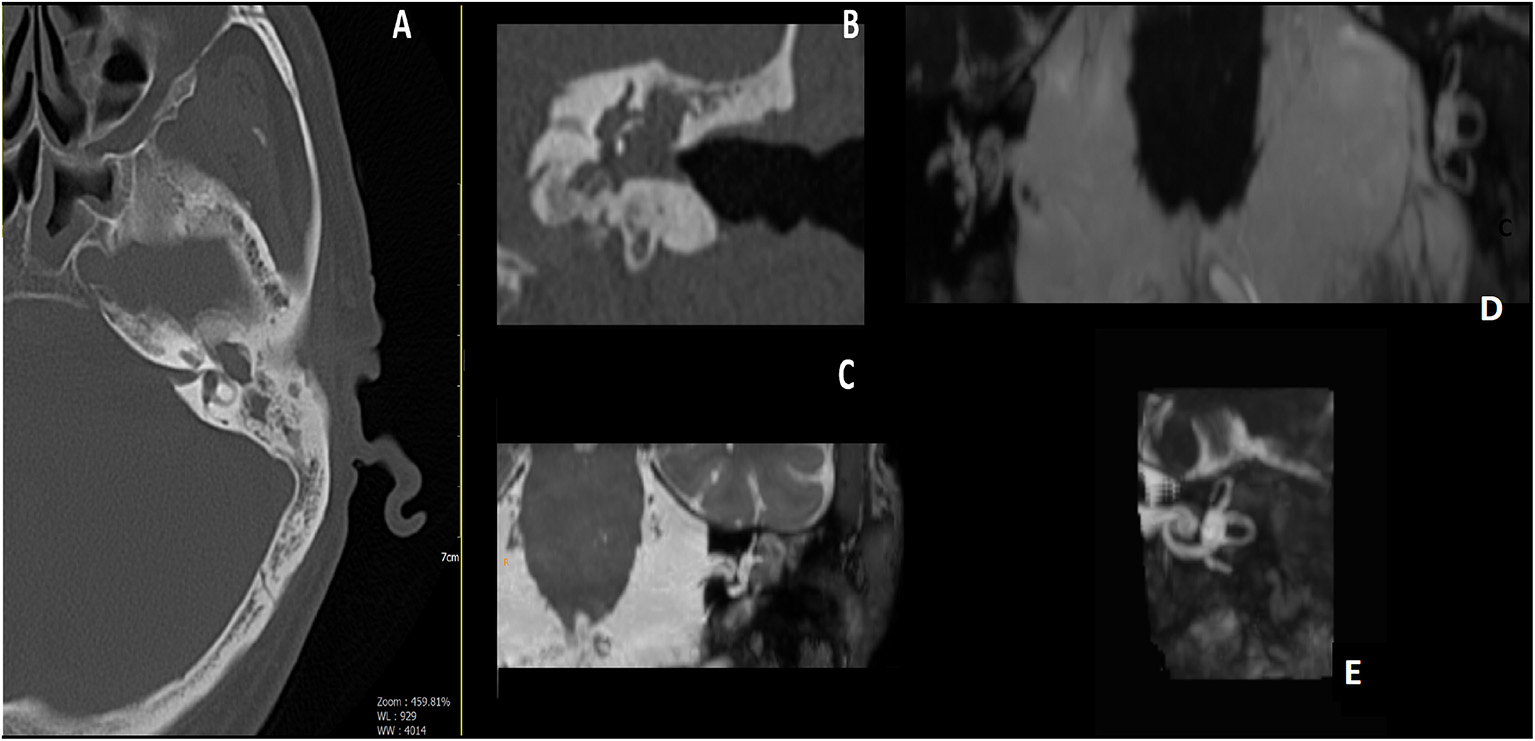

Figure 2

Male, 65 years old; (A) pre-operative axial CT scan, erosion of the bony lateral semicircular canal (LSC); (B) pre-operative Coronal CT scan, a well-evident erosion of the LSC; (C) pre-operative MRI, tissue appears to encase the LSC. (D) Post-operative MRI 3D Fiesta 3D sequences (field of view 20 × 20 cm TR 4 ms; TE 2 ms; flip angle 55°); (E) post-operative images Maximum Intensity Projection (MIP) for cochlea and semicircular canal visualization, detail of operated side, showing correct visualization of endocanal fluid preservation, and meaning preservation of hearing.